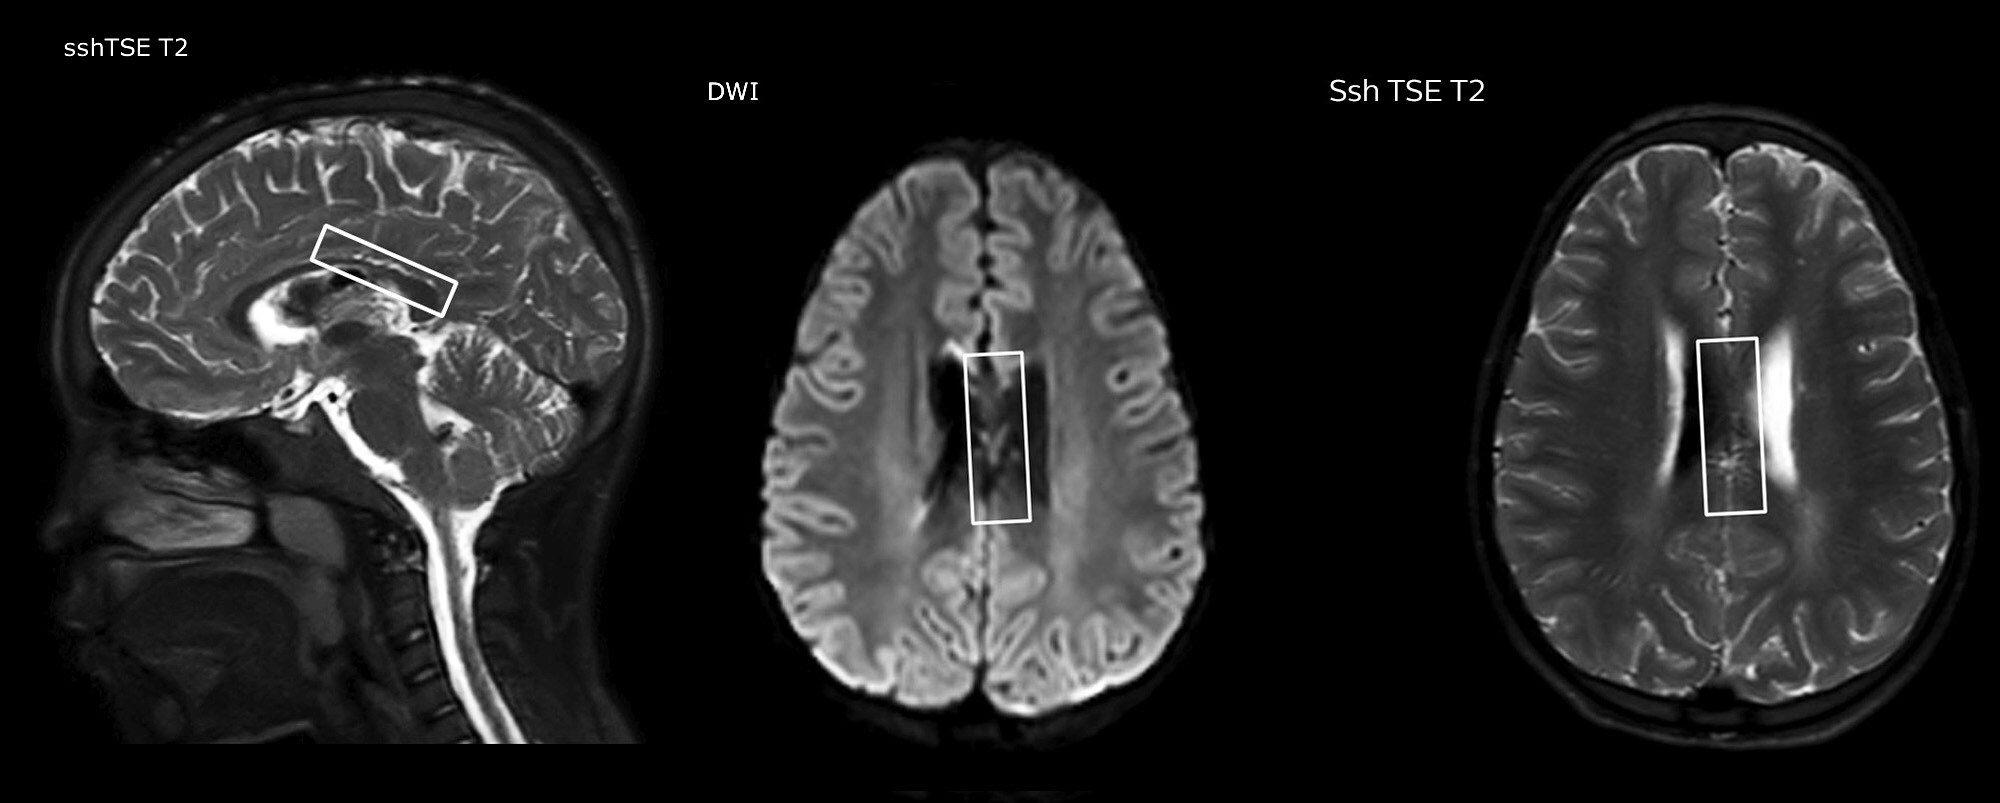

“In combination with diffusion weighted imaging, it can help give a more extended assessment of the degree of perfusion abnormality in a patient who is suffering acute ischemia. We have a number of patients who have chronic arterial insufficiency due to prior arterial abnormalities or acquired arterial abnormalities such as sickle cell disease or neurofibromatosis. Sometimes the child’s first manifestation of disease progression is a reduction in brain perfusion before stroke symptoms manifest clinically or in diffusion weighted imaging. We use pCASL to help delineate the perfusion abnormality.”